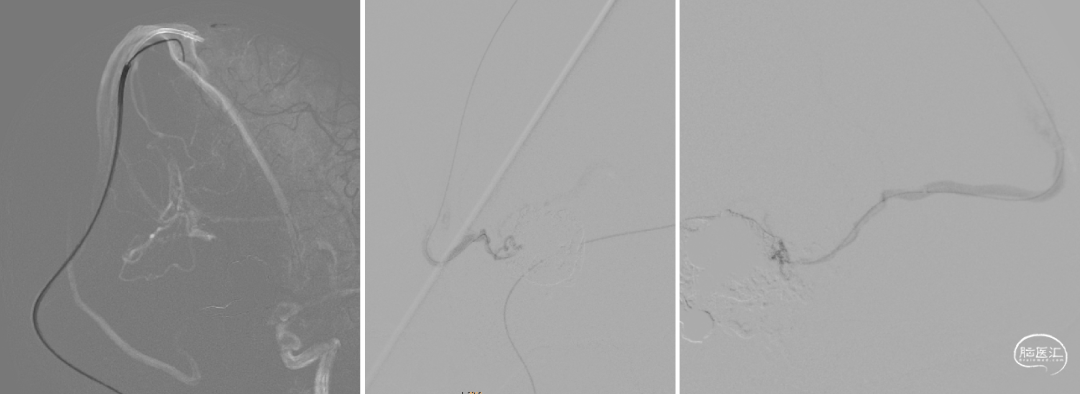

经静脉入路超选到位

经Echlon10微导管填入弹簧圈做塞子

经Apllo微导管注入Onyx胶